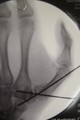

Hand surgery is a sub-specialty of plastic surgery. All plastic surgeons and orthopedic surgeons receive hand surgery training, but a select few decide to make hand surgery a focus area in their practice. Dr. Momeni had the privilege of training at Yale University under top New York metro area hand surgeons, and provides the following specialized hand surgery services:

- Fractures (broken bones) in the hand and fingers (not wrist)